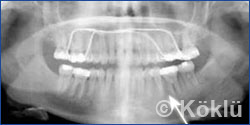

Trotz aller zahnärztlicher Kunst, müssen manchmal in bestimmten Fällen Zähne extrahiert (gezogen) werden, weil diese einen permanenten Entzündungsherd darstellen. Dieser fehlende Zahn muss dann natürlich ersetzt werden. Dafür gibt es verschiedene Möglichkeiten wie z. B. eine Brücke oder ein Implantat. Es gibt allerdings auch eine kieferorthopädische Alternative, welche in den nachfolgenden Röntgenaufnahmen dargestellt ist.

Auf dem ersten Bild wird dargestellt, wie mittels einer festen Klammer der 2. Backenzahn an die Position des 1. Backenzahns und der Weisheitszahn in die Position des 2. Backenzahns eingeordnet wird. Alle anderen Weisheitszähne wurden entfernt. Das zweite Bild zeigt den erfolgreichen Lückenschluss nach Behandlungsende.